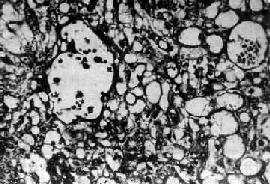

图13-23 内胚窦瘤

呈疏松网状粘液瘤样结构,其中有互相沟通、衬以上皮的腔隙及小囊腔,在瘤细胞内外可见嗜酸性玻璃样小球及基底膜样物